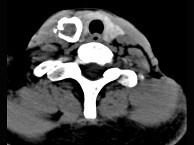

问题 50岁女性患者,体检发现右侧甲状腺有较硬结节,CT扫描如图所示,请选择正确的描述和答案()

选项 A.右侧甲状腺内见稍低密度影,周边围以环形致密钙化影 B.肿块影与周围结构分界清楚 C.考虑为结节性甲状腺肿 D.考虑为甲状腺癌 E.考虑为甲状腺腺瘤钙化

答案 ABE